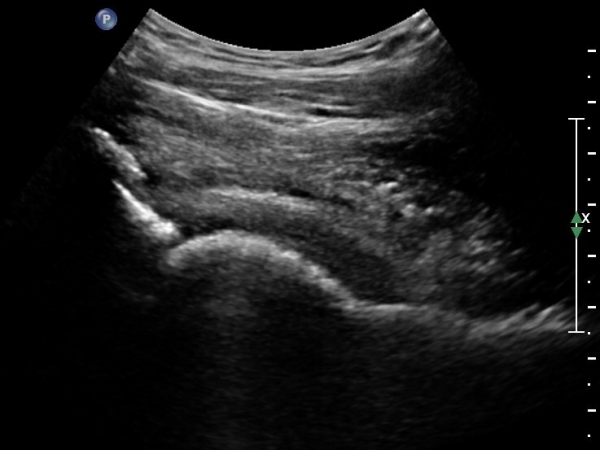

[¾ûµ¢ÀÌ] °í°üÀý Ãæµ¹ÁõÈıº¿¡ÀÇÇÑ È°¾×¸·¿° ÁÖ»çÄ¡·á

ÃÊÀ½ÆÄ °Ë»ç